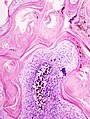

Seborrheic keratosis. H&E stain. | |

| LM | horn cysts, pigmented basal layer, hyperkeratosis |

Microscopic

Features:[2]

- Raised above skin surface.

- Border sharply demarcated.

- Hyperkeratosis - stratum corneum extra thick.

- Horn cysts - intraepidermal collections of keratin - key feature.

- Actually invaginations - not true cysts; thus, they may more accurately be called pseudohorn cysts.[4]

- Clusters of cells with brown granular material in the superficial dermis/dermoepidermal junction - pigmented melanocytes.